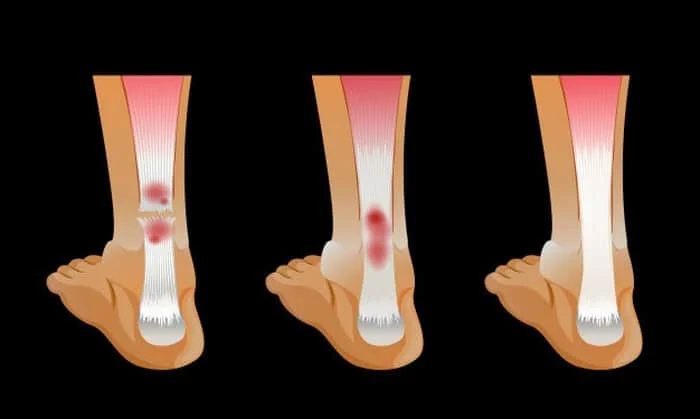

شکستگی باز (مرکب) :

استخوان شکسته از طریق پوست خارج می شود و  احتمال عفونت و خونریزی خارجی بیشتر است .

شکستگی بسته (ساده) :

استخوان شکسته اما پوست را سوراخ نکرده است .

شکستگی گرین استیک :

ترک کوچک و باریکی در استخوان است که این ممکن است در کودکان رخ دهد زیرا استخوان های آن ها از استخوان های بزرگسالان انعطاف پذیرتر می باشد .

شکستگی پیچیده :

در این شکستگی ساختار اطراف بافت آسیب دیده یا شکسته شده اند و ممکن است به رگ ها، سرخرگ ها یا اعصاب آسیب برسد و همچنین ممکن است پوشش استخوان آسیب دیده شود .

شکستگی کنده شده :

عضلات با استخوان تاندون که  نوعی بافت همبند است ، به استخوان لنگر می اندازند . انقباضات عضلانی قدرتمند می تواند تاندون را از بین ببرد و قطعات آن را بیرون بکشد . این نوع شکستگی بیشتر در مفاصل زانو و شانه دیده می شود .

شکستگی مویی :

شایع ترین شکل شکستگی است و قسمت های شکسته شده جابه جا نشده اند و نیرویی که موجب این شکستگی شده قوی نیست.